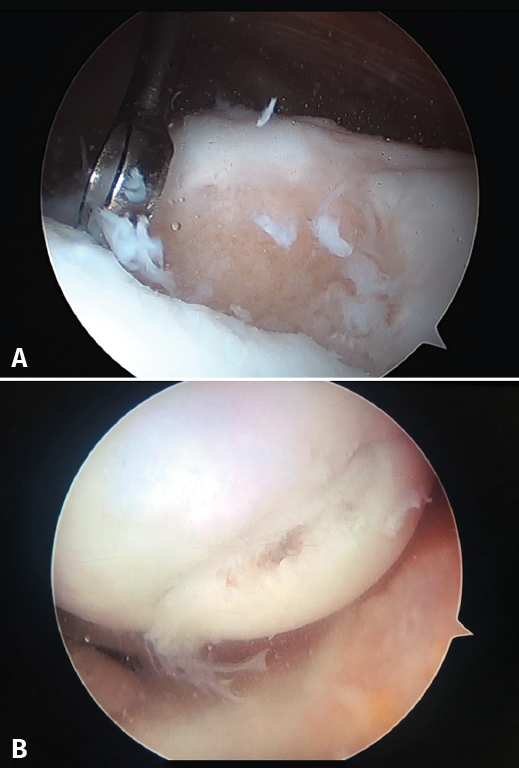

Figure 4. Arthroscopic views of the Outerbridge chondral lesion grades. A: grade I lesion; B: grade II lesion; C: grade III lesion.

Figure 4 shows arthroscopic images of lesions corresponding to grade II (Figure 4A), grade III (Figure 4B) and grade IV (Figure 4C).